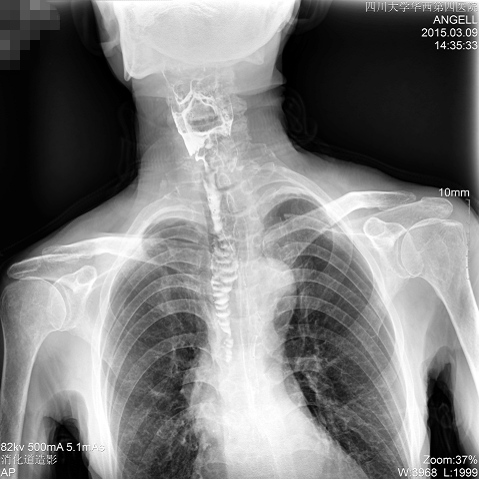

如下圖所示:該患者因吞咽時感到很難受,進食時也經(jīng)常咳嗽故就醫(yī)診斷。使用多功能dr為病人進行消化道造影診斷,要求他吞鋇后發(fā)現(xiàn),食道各段通過順利,形態(tài)規(guī)則,雙側(cè)梨狀窩不對稱左側(cè)稍淺,多次吞咽動作后,仍見鋇劑滯留,并見鋇劑進入氣管,屬于會厭征陽性。會厭功能紊亂,鋇劑進入了氣管。

圖為斜位:通過動態(tài)影像可以清楚看到鋇劑進入了支氣管道

通過多功能dr可以診斷該病人的癥狀為會厭功能紊亂,鋇劑進入到了氣管。而在動態(tài)透視下可以清晰的觀察到鋇劑從何處進入氣管,可清晰顯示食管粘膜結(jié)構(gòu)。使用多功能dr其獨特的視頻采集技術(shù),可實時保存視頻并能實現(xiàn)900萬像素實時點片,才能獲取這樣清晰的病灶點。而常規(guī)dr只能拍攝靜態(tài)片,且成像效果大打折扣,因此較難確診病灶。